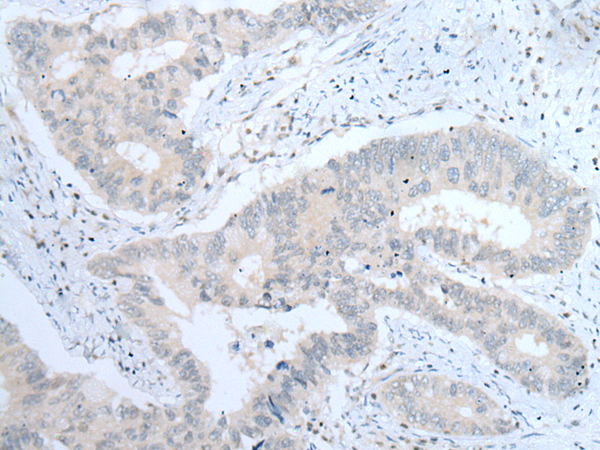

ELISA, IHC |

IHC positive control: |

Human colorectal cancer |

IHC Recommend dilution: |

25-100 |